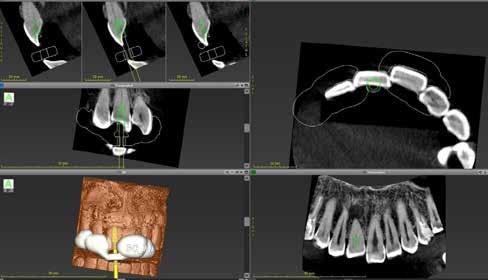

Kalcifikált felső metszőfog kiszámítható gyökérkezelése

3D-nyomtatott

fúrósablon segítségével